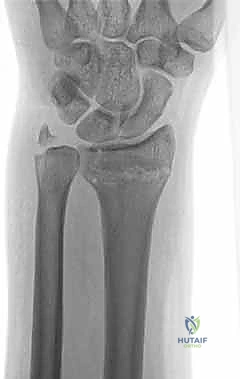

1. الأشعة السينية (X-rays): بوضعيات متعددة (أمامية خلفية، وجانبية دقيقة). الوضعية الجانبية الحقيقية (True Lateral) حاسمة لاكتشاف أي خلع جزئي في المفصل (DRUJ).

أولاً: العلاج التحفظي (غير الجراحي - Conservative Treatment)

يتم اللجوء إلى هذا الخيار في الحالات التالية:

* كسور قمة الناتئ الإبري المستقرة.

* كسور الجزء الكردوسي أو رأس الزند التي لا يوجد بها انزياح (Non-displaced fractures).